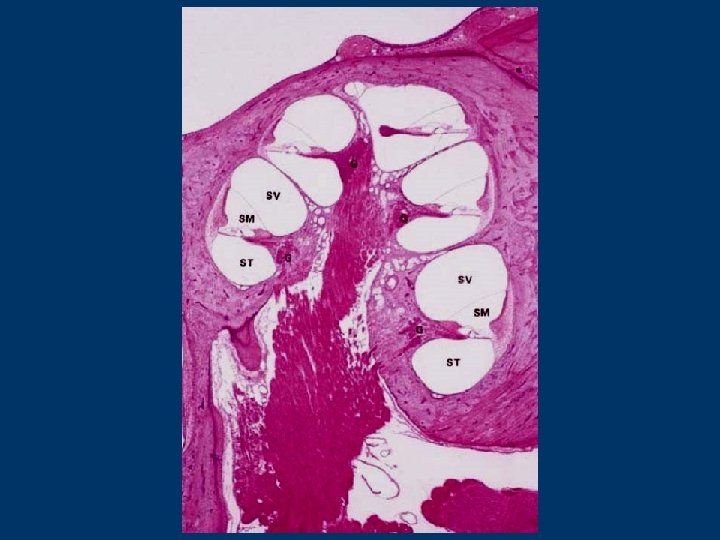

Cochlear duct this compartment of the membranous labyrinth appears to be as diverticulum of the saccule, it is blind and filled with endolymph, about 35 mm long is housed within cochlea it serves as sound receptor The cochlea (saggital section): the cochlear spiral canal - is about 35 mm in total length and makes 2. 5 turns around bony core the modiolus (is penetrated by spaces (chanels) containing blood vessels and cell bodies and processes of acoustic branch of the 8 th cranial nerve - spiral ganglion) the osseous spiral lamina - extends laterally from the modiolus 3 spaces are in the cochlear spiral canal: -- the scala vestibuli - turned to the apical part of the cochlea -- the scala media = cochlear duct -- the scala tympani - turned to the base of the cochlea both scalae communicate each other via opening known as the helicotrema - situated at the apex of the cochlea around the chochlear duct is the perilymph scalae are in realty one long tube, beginning at the oval window and terminating at the round window

The cochlear duct has triangular profile in sagittal section 3 walls : n a vestibular membrane (Reissner´s membrane) n a lateral wall n a tympanic wall - including the basilar membrane with the organ of Corti peripherally - the osseous spiral lamina centrally